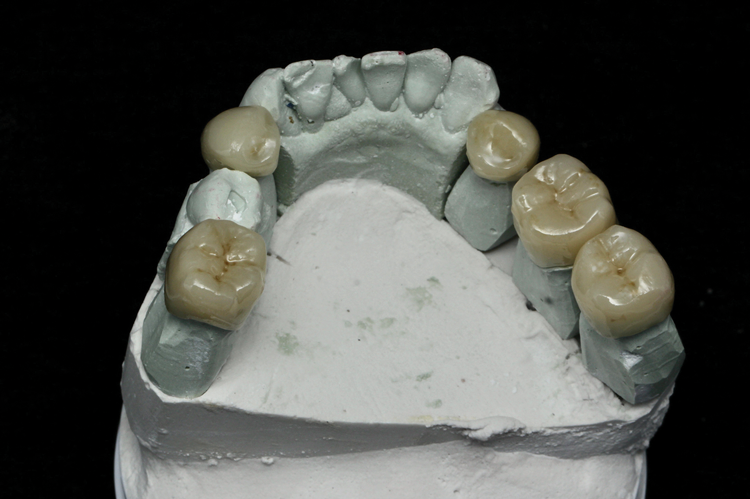

(3.) Facial, incisal, and intaglio views of the composite veneers that were designed and milled for teeth Nos. 6 through 11.

Figure 3

(4.) Facial, incisal, and intaglio views of the composite veneers that were designed and milled for teeth Nos. 6 through 11.

Figure 4

(5.) Facial, incisal, and intaglio views of the composite veneers that were designed and milled for teeth Nos. 6 through 11.

Figure 5